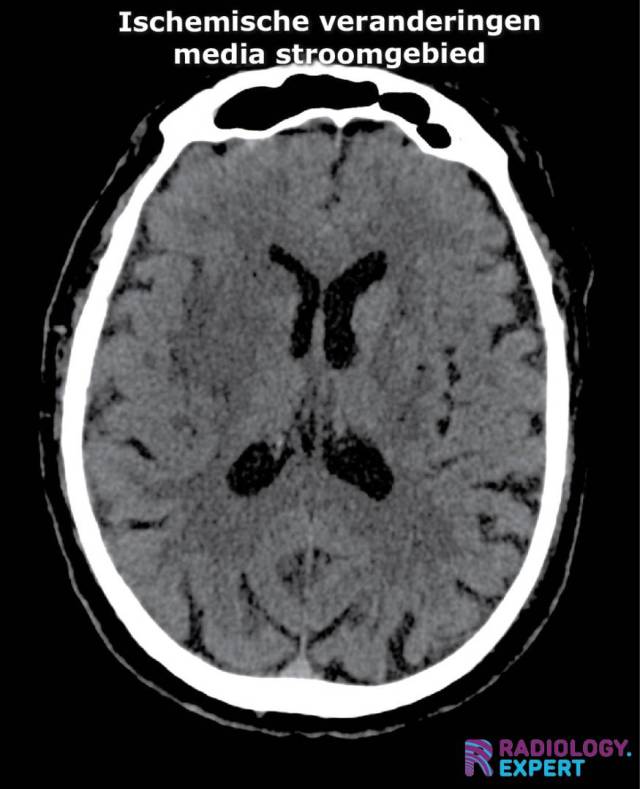

ischemische veranderingen op CT bij media infarct. Insular ribbon sign. Verstrijking basale kernen ischemische veranderingen op CT bij media infarct. Insular ribbon sign. Verstrijking basale kernen

Klik op afbeelding om overlay te zien